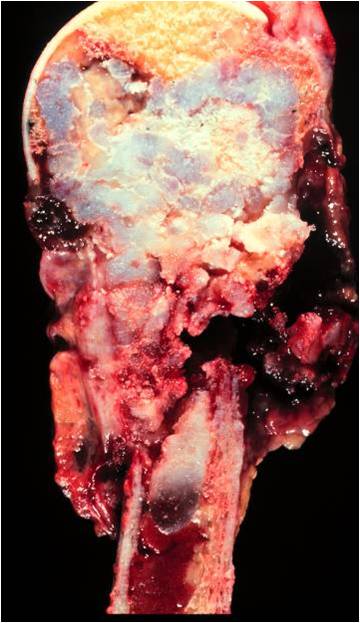

Gross Pathology

- Areas with typical lobular, blue-gray myxoid hyaline cartilage tissue

- Or overtly cartilaginous appearance of mature hyaline cartilage

- Zones of brown, tan, or hemorrhagic tissue

- Lacking the consistency of cartilage

- Dedifferentiated component may only be a minor portion of the overall tumor

- May also be so extensive that little cartilage is recognizable